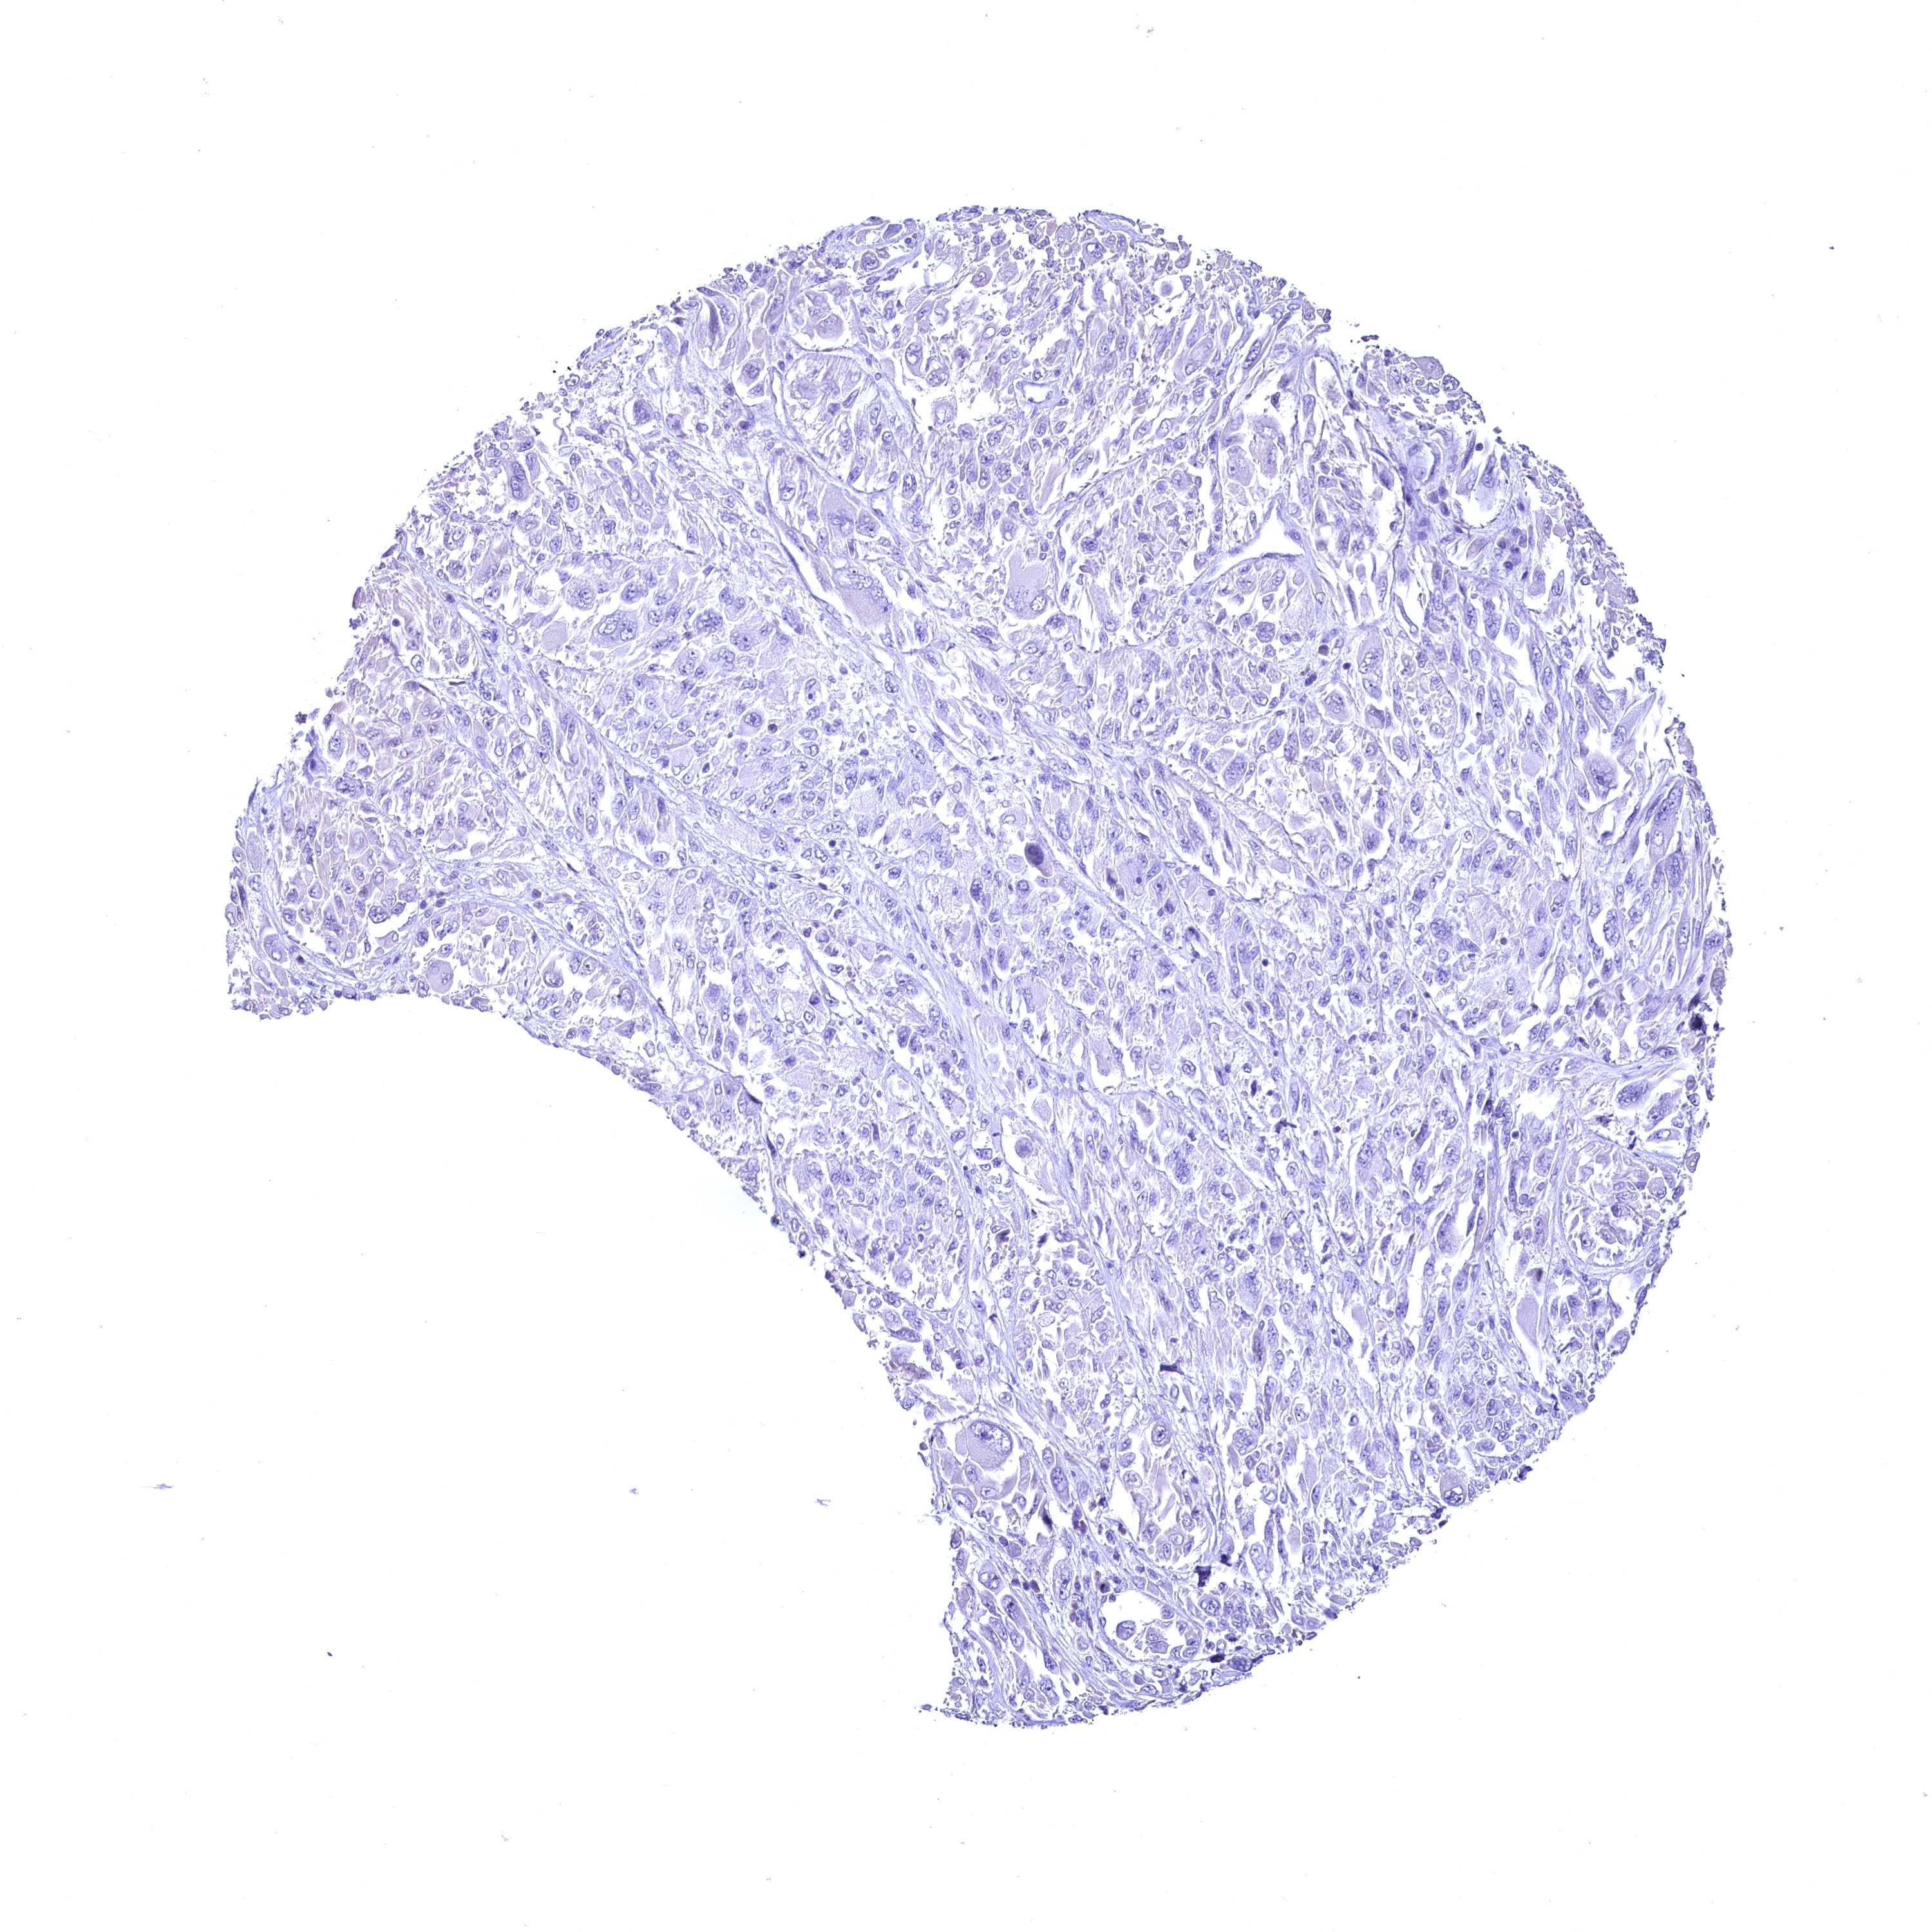

MELANOMA - Protein expressioni

A mouse-over function shows sample information and annotation data. Click on an image to view it in a full screen mode. Samples can be filtered based on level of antibody staining by selecting one or several of the following categories: high, medium, low and not detected. The assay and annotation is described here.

Note that samples used for immunohistochemistry by the Human Protein Atlas do not correspond to samples in the TCGA dataset.

Antibody stainingi

Antibody staining in the annotated cell types in the current human tissue is reported as not detected, low, medium, or high, based on conventional immunohistochemistry profiling in selected tissues. This score is based on the combination of the staining intensity and fraction of stained cells.

Each image is clickable and will lead to virtual microscopy that enables deeper exploration of all samples and also displays staining intensity scores, fraction scores and subcellular localization as well as patient and tissue information for each sample.

Antibody HPA039208

Antibody HPA040439

Staining

High

Medium

Low

Not detected

Intensity

Strong

Moderate

Weak

Negative

Quantity

>75%

75%-25%

<25%

None

Location

Nuclear

Cytoplasmic/membranous

Cytoplasmic/membranous,nuclear

Malignant melanoma, NOS

Malignant melanoma, Metastatic site